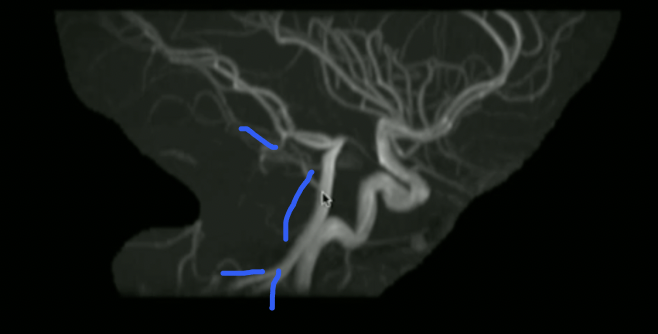

<p>What is the orientation + what are these vessels?</p>

What is the orientation + what are these vessels?